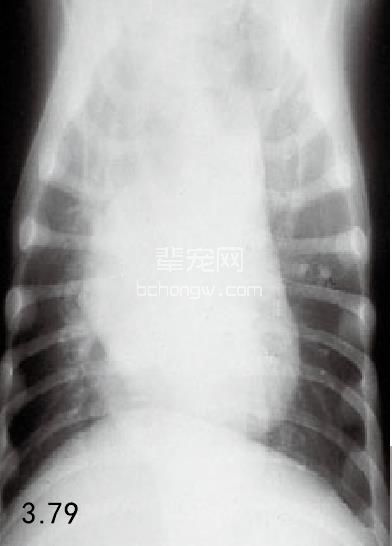

诊断 通过病史和胸腔常规X线片可以诊断 (图3.77~图3.80),但如果需要确定特殊的病 因,则需要进行额外的试验(表3.7)。如果不能 确诊可以做食管X线片和食管镜试验,但通常没有 这个必要(图3.81和图3.82)。德国牧羊犬、大丹 犬、爱尔兰赛特犬、小型雪纳瑞犬和硬毛 易患 先天性巨食管症。犬胃扩张-扭转综合征时,也 可能暂时性继发巨食管症。

图3.78和图3.79 在图3.77中所述幼犬的食道造影X线片可见食管的巨大扩张。